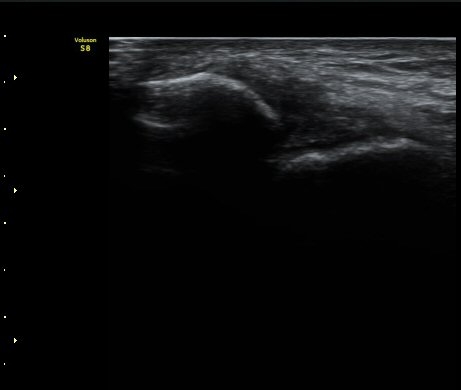

Àü°Å°ñºñ°ñÀδë Á¾´Ü¸é°Ë»ç»ó Àδë ÀδëÀÇ Àú¿¡ÄÚ ºÎÁ¾°ú(±×¸² 3)

ºñ°ñºÎÂøºÎ ¿¬°á¼º ¼Ò½ÇÀÌ °üÂûµÈ´Ù(±×¸² 4).

±×¸²3) Àü°Å°ñºñ°ñÀδë Á¾´Ü¸é°Ë»ç

±×¸²4) Àü°Å°ñºñ°ñÀδë Á¾´Ü¸é°Ë»ç